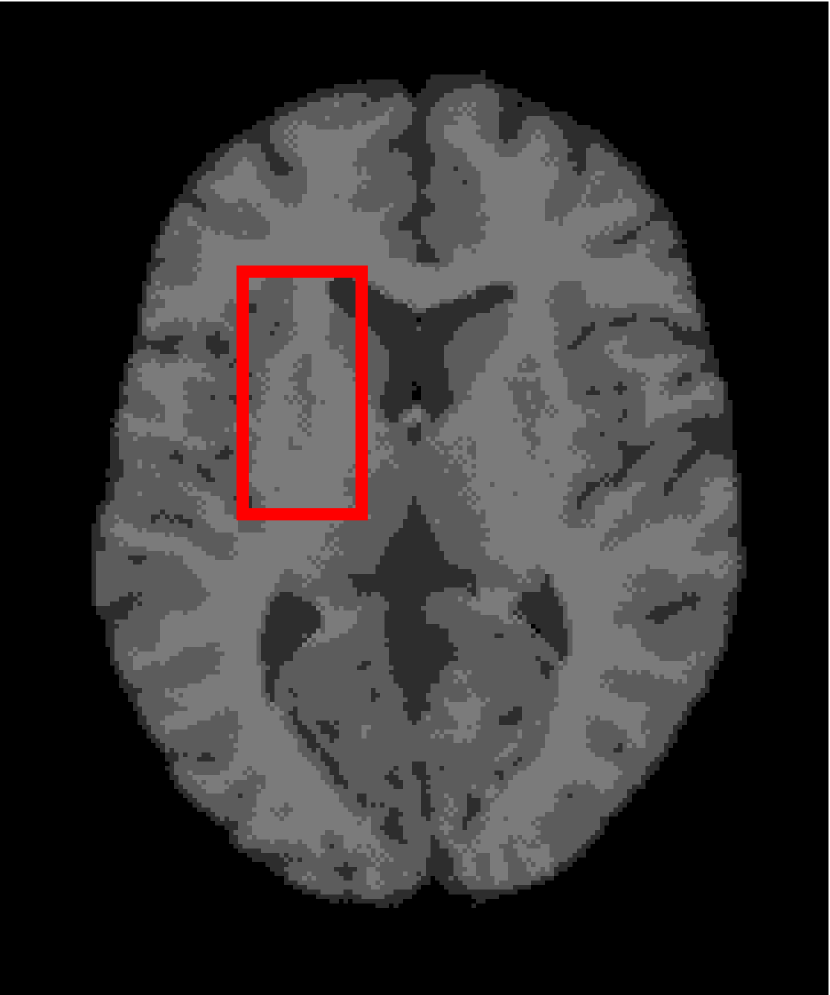

Next, we representatively segment five medical images from BrianWeb. They are represented as five slices in the axial plane with a sequence of 70, 80, 90, 100 and 110, which are generated by T1 modality with slice thickness of 1mm resolution, 9% noise and 20% intensity non-uniformity. Here, we set c=4𝑐4c=4 for all cases. The comparison between WRFCM and its peers are shown in Fig. 9 and Table II. The best values are in bold.

Figure 9: Segmentation results on five medical images. The parameter: ϕ=5.35italic-ϕ5.35\phi=5.35. From top to bottom: noisy images, ground truth, and results of FCM_S1, FCM_S2, FLICM, KWFLICM, FRFCM, WFCM, DSFCM_N, and WRFCM.

By a view of the marked red square in Fig. 9, we find that FCM_S1, FCM_S2, FLICM, KWFLICM and DSFCM_N are vulnerable to noise and intensity non-uniformity. They give rise to the change of topological shapes to some extent. Unlike them, FRFCM and WFCM achieve sufficient noise removal. However, they produce overly smooth contours. Compared with its seven peers, WRFCM can not only suppress noise adequately but also acquire accurate contours. Moreover, it yields the visual result closer to ground truth than its peers. As Table II shows, WRFCM obtains optimal SA, SDS and MCC results for all five medical images. As a conclusion, it outperforms its peers visually and quantitatively.